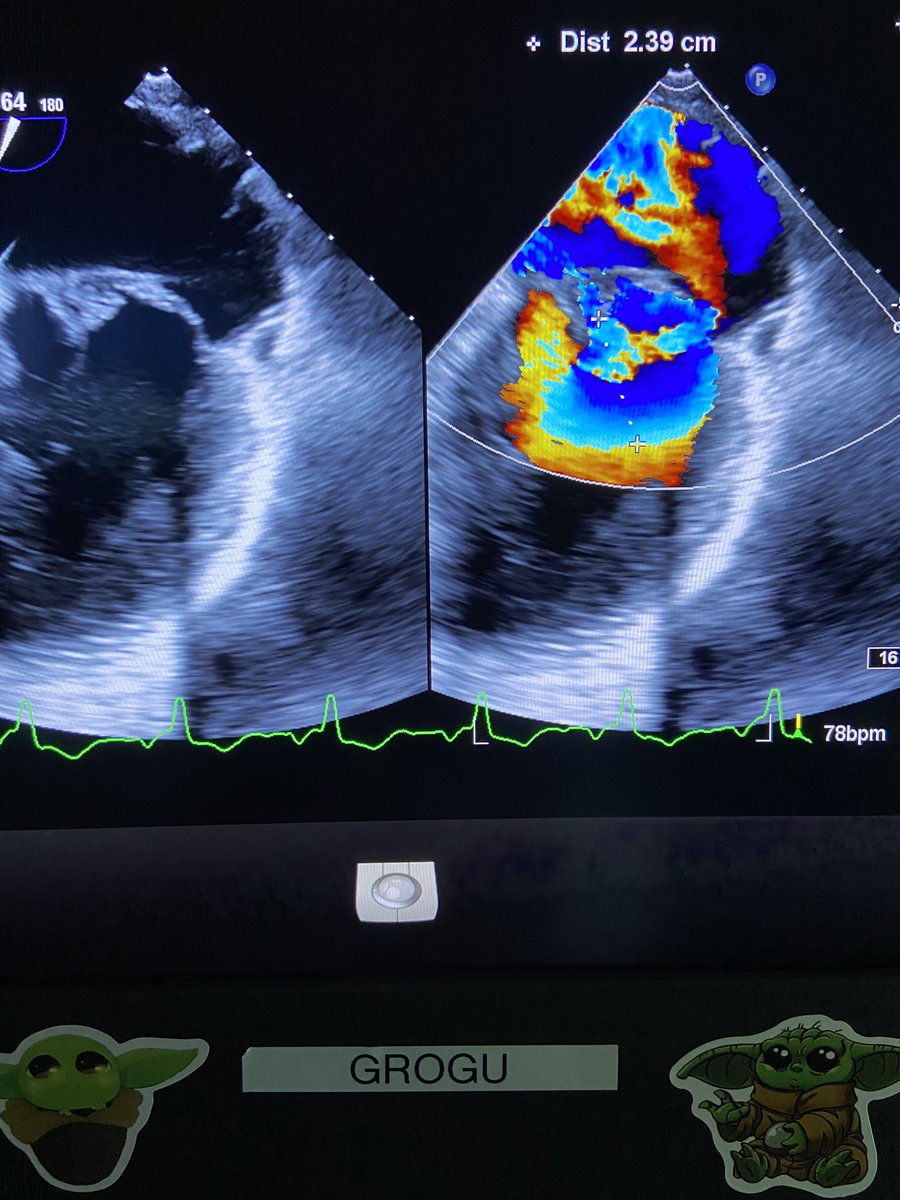

Severe MR - if you look close, theres a PISA shell inside a PISA shell. My last TEE as an imaging fellow @HeartPlano with @ZuyueWangMD & GROGU. #echofirst #cardiacimaging @EchofirstB